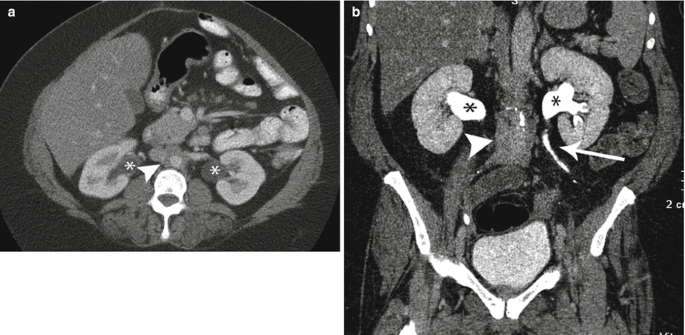

Congenital Anomalies of the Upper Urinary Tract: A ...